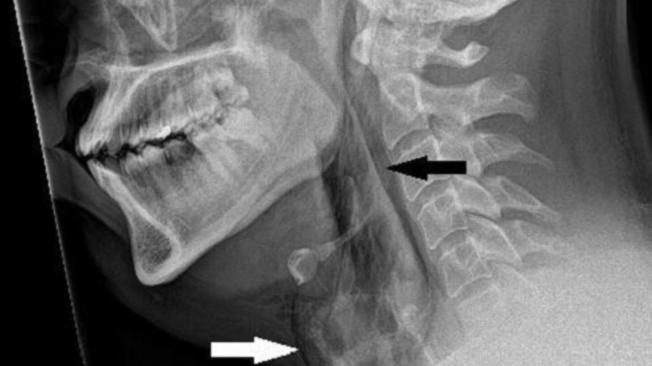

En las radiografías que le practicaron se confirmó que se trató de un enfisema quirúrgico.

En resumidas cuentas, el aire quedó atrapado debajo de las capas de tejido más profundas de la piel, ocasionándole un desgarro entre el tercer y cuarto hueso de la vértebra del cuello.